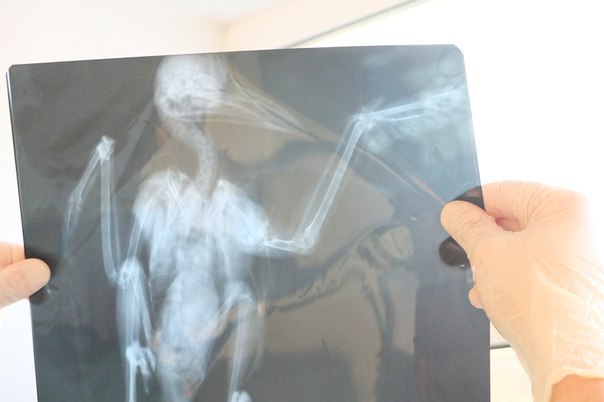

Черную как смоль птицу нашли 29 января на улице Владимировской. У вороны было перебито крыло. Один из общественников откликнулся на призыв и выехал на место. Птицу отвезли в ветклинику – после рентгена выяснилось, что ворону расстрелял неизвестный и перебил ей крыло. Вынесенный доктором Козловым диагноз был неутешителен: «перелом открытый оскольчатый правой плечевой кости. Остеомелит».

Как рассказала участница ОД «Права животных» Анна Массольд, перелом у вороны оказался старым — ему уже несколько недель и в организме были запущены дегенеративные процессы, которые могли привести к летальному исходу. Действовать нужно было как можно быстрее.

Позавчера, 9 февраля в клинике «Бэст» вороне была проведена операция. Клиника в разы уменьшила стоимость проведенной процедуры. На вопрос, почему, Евгений Козлов ответил: «Ворона птица бесценная, я решил ее спасти».

Операция прошла успешно. Сейчас Карлуша (так назвали птицу) находится на базе реабилитации «Права животных» и восстанавливается после операции. Через две недели предстоит снятие швов. По словам Анны Массольд, отпускать ворону на волю не планируется — она просто погибнет.